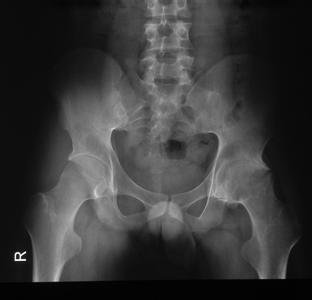

临床检查:背部弯曲严重,左眼视力4.0、患有虹膜炎;X片检查显示骶髋关节和脊柱融合,关节遭到严重破坏、增生硬化、骨质明显疏松、关节完全强直;实验室检查:红细胞沉降率达50mm/h, C反应蛋白(CRP) 高达50mg/l。

(图:X线片显示骶髋关节融合,完全强直)